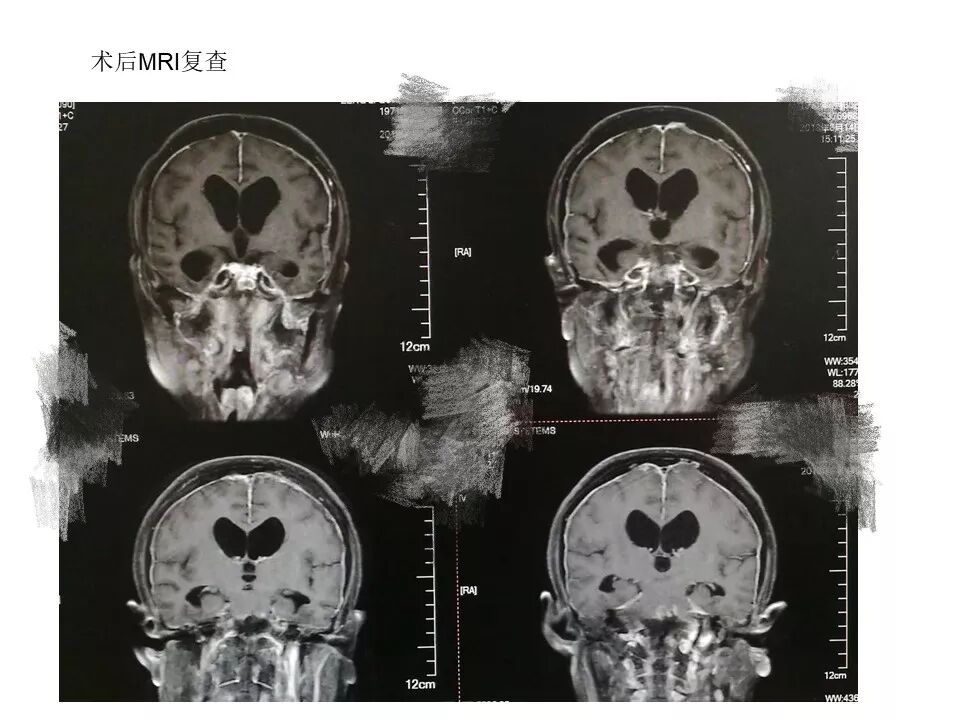

今天为大家分享的是《贝朗时间》第三十八期,由中国人民解放军武汉总医院神经外科副主任姚国杰教授带来的:远外侧入路全斜坡巨大脑膜瘤显微手术1例,欢迎阅读、分享!

远外侧入路全斜坡巨大脑膜瘤显微手术1例